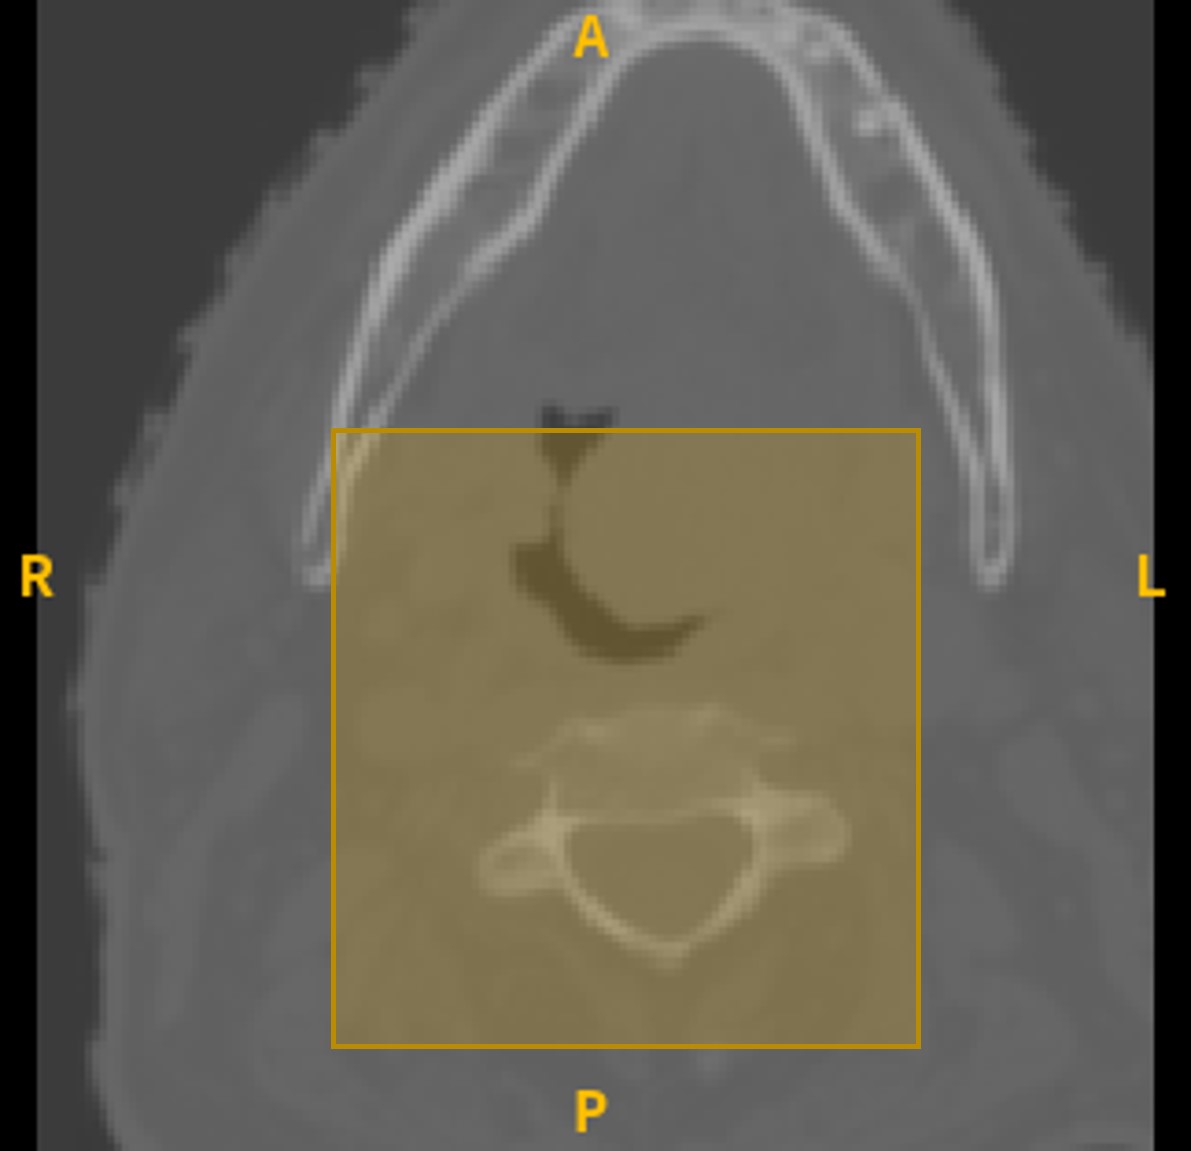

Refer to caption

((a)) CT

((b)) PET

((c)) Fused

Figure 4: An example of combining CT and PET scans. (a) depicts the (144x144x144) CT scan with a rectangle to show the region to be cropped. (b) shows the (144x144x144) PET scan and the cropping region. (c) shows the (80x80x50) fused image in the cropped form.

As for the image dataset, PET and CT scans were preprocessed using the bounding box information available in the provided csv file to obtain 144x144x144 cropped images. To prepare the image data for our model input, we normalized the two images to the same scale and a fused image was created by averaging the two scans for each patient. To further reduce the volume, the fused output image is cropped again based on a specific distance away from the center of the 144x144x144 cube as shown in Fig. 4. Two possible crop resolutions were considered: 50x50x50 and 80x80x50; however, the latter was adopted since it resulted in a better outcome.